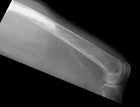

A.M. - 87 year old female with an asymptomatic posterior thigh soft tissue mass present for many years, the patient reports that it has increased in size over the past three months